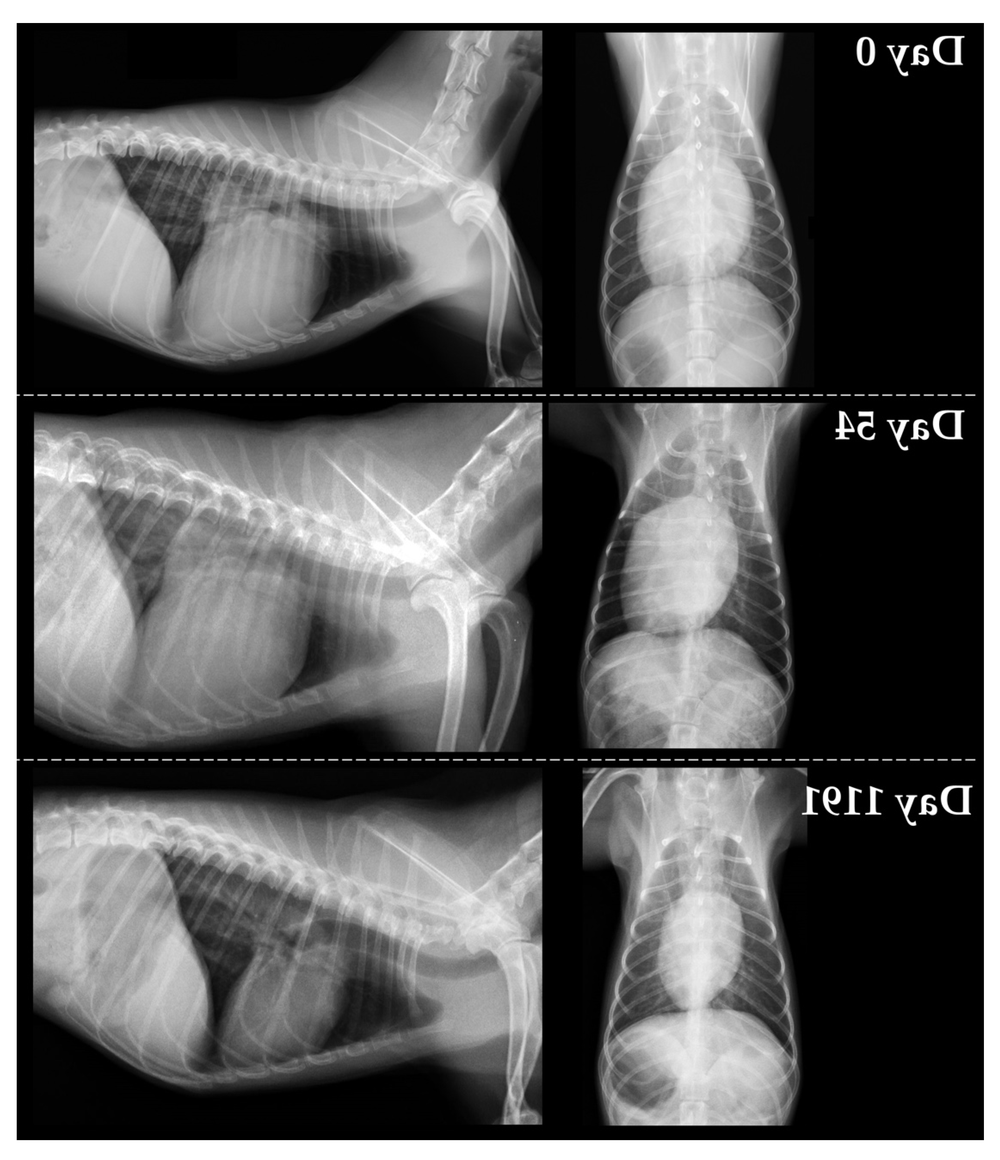

• Echocardiogram (heart ultrasound), this is the most definitive way to assess chamber size and pumping function for DCM.1

• Chest X-ray to check heart size and look for fluid in the lungs when heart failure is suspected.1